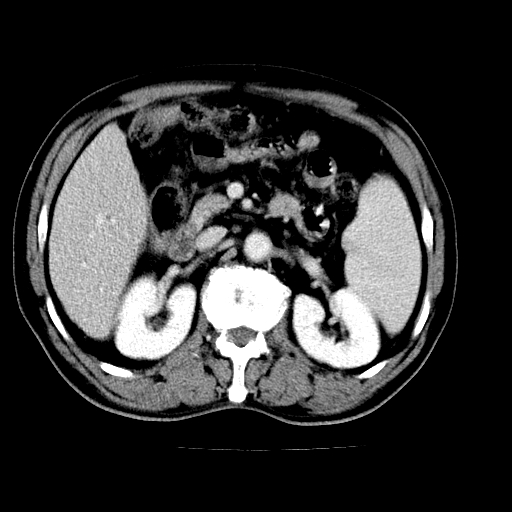

男,66岁,上腹部不适、黄染一周。彩超示:肝左叶占位,肝内胆管扩张,胆总管扩张,胆总管占位?

肝左叶不规则软组织肿块影,边缘不规整邻近肝实质受累分界不清;肝内胆管(左叶)明显扩张成“软藤状”,诊断:肝左叶胆管细胞癌。

肝左叶占位性病变,并胆管扩张,符合胆管细胞癌ct表现,门脉左支受累,左肾囊肿。窗宽太窄了,其他的看不清

左叶胆管细胞癌累及胆总管,门脉左支受侵,慢性胆囊炎胆结石,左肾小囊肿